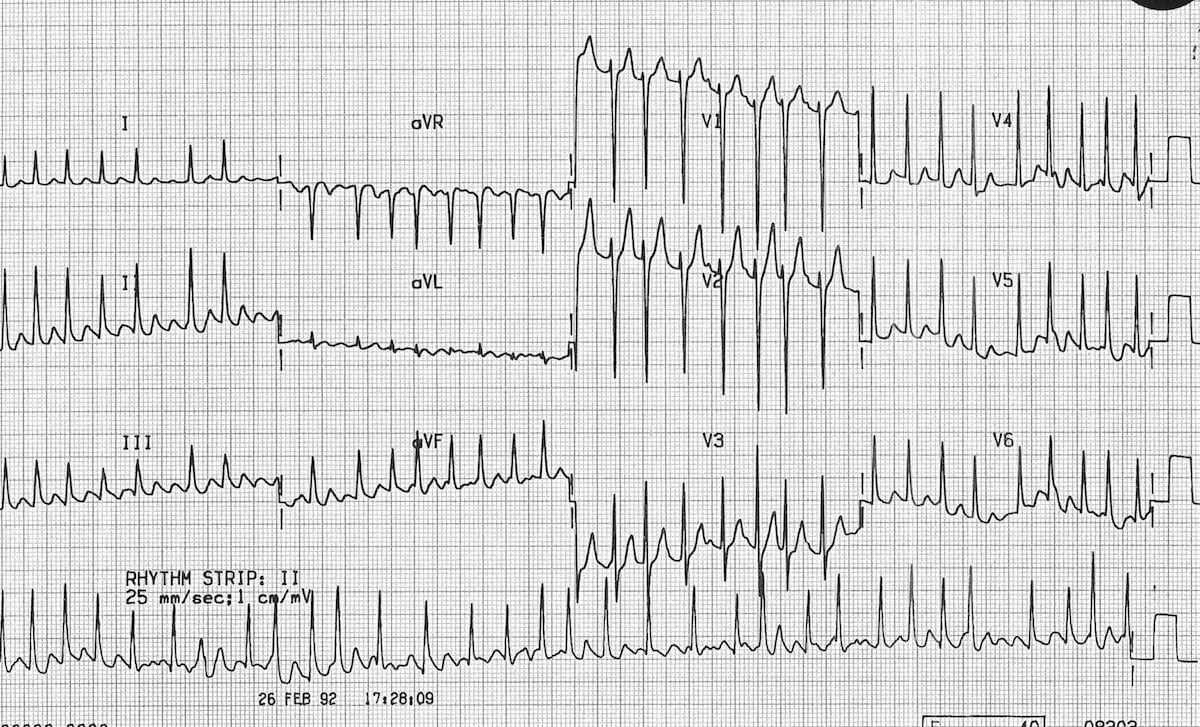

ECG Examples

Example 1

Example 2